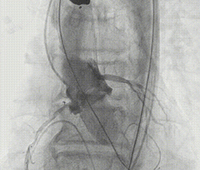

通过支撑导丝,送入23mm SAPIEN 3瓣膜,使用独特调弯功能,保证安全过弓并成功跨瓣;调整至共平面角度,瓣膜到位,快速起搏下+1cc精准释放瓣膜。

图片

撤出导丝后,造影超声结果均显示瓣膜工作良好,瓣膜释放后流入/流出比例=90 :10,术后导管测量压差6mmHg,经胸超声检测微量瓣周漏,无冠脉阻塞、无支架植入、无起搏器植入、无并发症,手术成功。